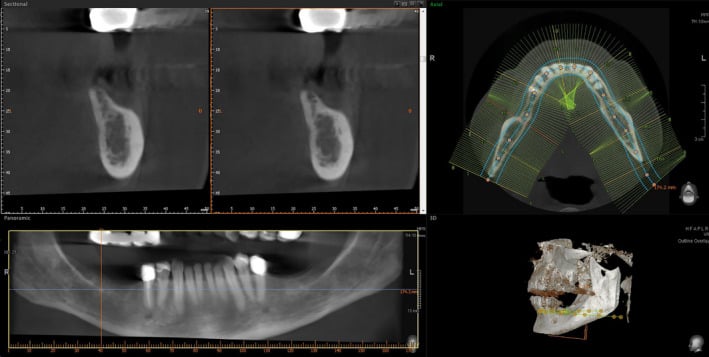

Figure 1.

Preoperative CBCT: vertical bone defects in the third and fourth quadrant

Figure 4.

CBCT before implantation: significant vertical bone gain after 4 months of healing in both quadrants